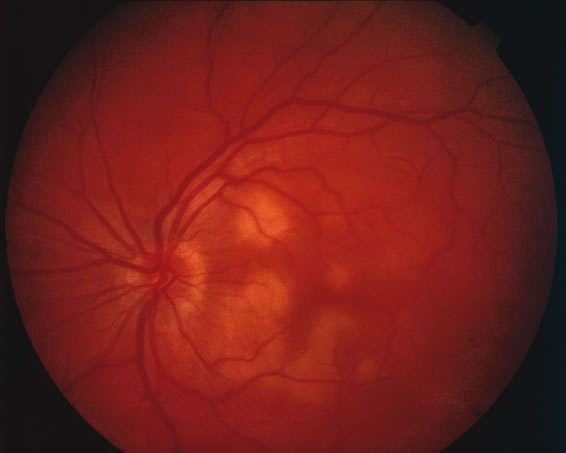

Acutely, there may be creamy white lesions in the posterior pole. These lesions tend to be deep and poorly demarcated. Sometimes these lesions may become confluent. The lesions clear by losing their yellow-white opacification and clearance occurs from centrally to the periphery. With time the lesions resolve leaving mottling of the retinal pigment epithelium (Figs. 5, 6, and 7).

Fig. 5. Fundus photograph showing the acute creamy lesions of a recent case of acute multifocal posterior placoid pigment epitheliopathy.

Fig. 6. Fundus photograph of the same case as in Figure 5. The findings at 1 month after the initial presentation now shows mild pigment clumping and mild retinal pigmentary atrophy.